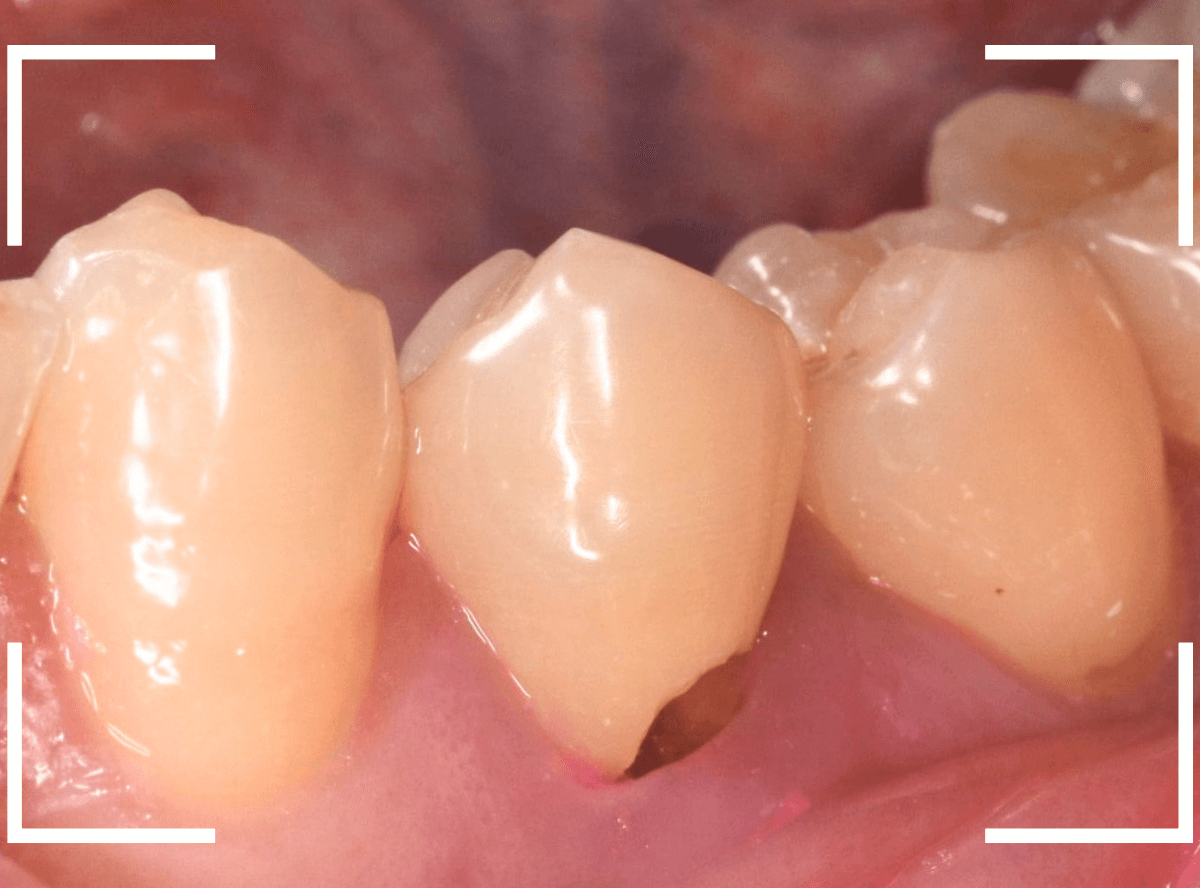

実際の治療例 神経をとらなければいけないほど、大きな虫歯がわからない

「歯がとても痛む」という患者さんが来院されました。

初見では、特に大きな虫歯や歯周病という感じではありませんでした。

しかし、ピンセットで歯を叩くと、確実にこの歯で反応があります。

レントゲン写真でも、大きな虫歯などはなさそうな感じです。

もう一度歯を確認すると、つけ根がうっすらと虫歯っぽいです。

これかな?しかし、風をかけてもしみません。

うーん。。。

レントゲン写真ももう一度確認してみます。

もしかすると、歯肉の中で虫歯が広がってるのかもしれません。

側面からの虫歯ですので、どれくらい虫歯が深いのかはこの写真からはわかりません。

患者さんに状況をお話しし、麻酔をして慎重に歯を削って調べてみると、神経まで達する虫歯でした(><)

これが痛みの原因で間違いなさそうです。

しみるなどの症状が出る事なく、歯の側面が神経まで達する虫歯になる事は珍しいです。

虫歯と神経を除去し、蓋をして何回か、神経の治療が続く旨ご説明し、今日は治療終了です。

今回は、明確な痛みがあったためにまだ診断がつきやすかったですが、そうでない事もあります。

虫歯の診断も奥が深いです。